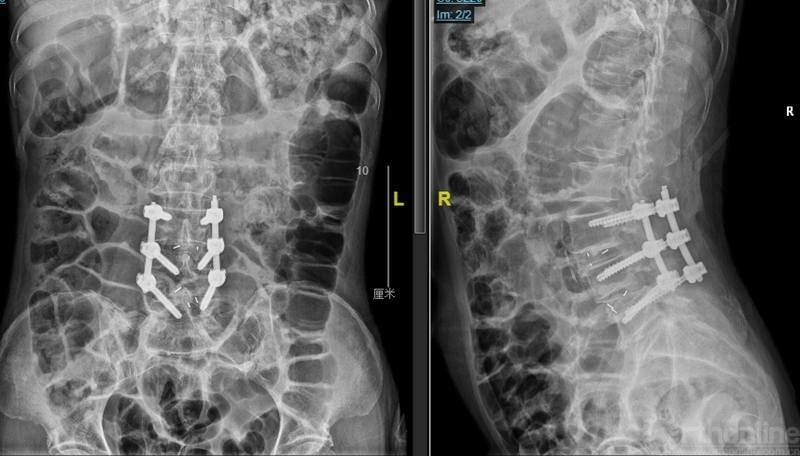

图4:第一次术后X ray

观察24小时后无明显改善,再次行开放腰椎全椎板扩大减压术,近端矢状面扩大减压延伸过腰椎矢状面顶椎(图8),左侧腰4、5及骶1神经根管扩大减压,直至肉眼辨别无明显交界区卡压和神经根紧张(图9)。

图8:第二次减压近端延伸至腰2椎体后方,保留腰1-2小关节完整

图9:第二次减压腰2至腰5全椎板减压,腰2-3小关节保留

第二次术后,患者的双下肢症状即明显的开始进行性恢复和改善。

本病例显示:因MIS-TLIF工作通道的远近端摆动角度的范围决定了矢状面头尾端的减压范围,若面对高PI显著腰椎前凸的多节段腰椎管狭窄的病例,近端扩大减压会受到一定限制。